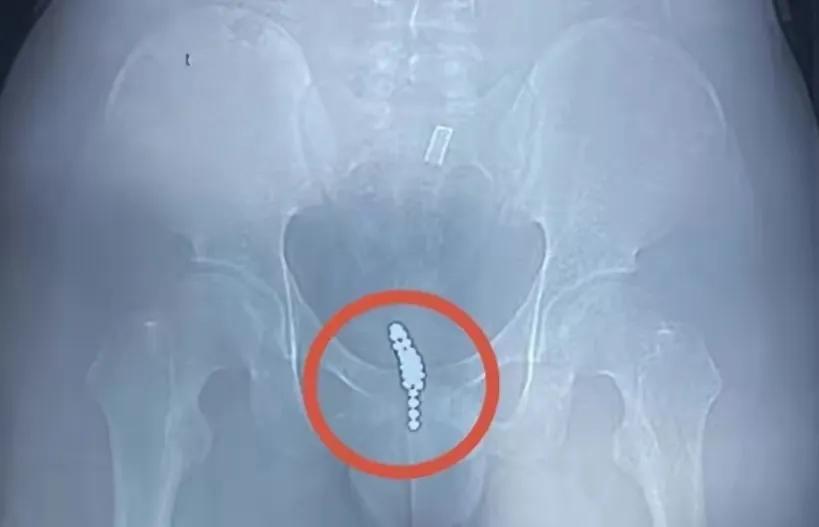

18岁男生从尿道口塞入25颗磁力珠

由于好奇,他将一颗“磁力珠”塞入自己的尿道,然而却无法取出,惊慌之下又连塞了几颗,企图利用磁力将珠子给吸出来。

结果连塞了20多颗都没能将磁力珠给吸出来,还出现尿频、尿急和血尿等情况,他无奈只得告诉父母。